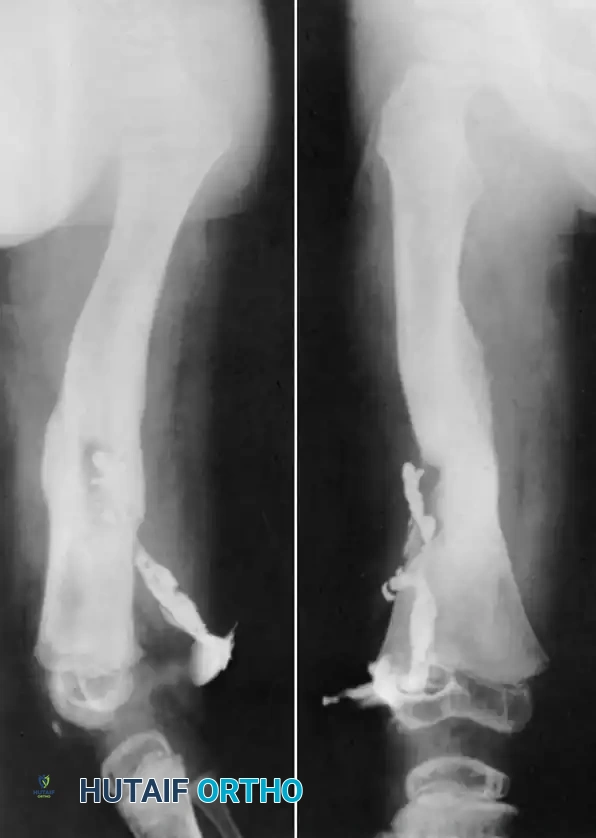

- Plain Radiographs: The mandatory initial study. Signs of focal osteopenia, cortical destruction, periosteal reaction, and the presence of a sequestrum strongly suggest the diagnosis.

- Computed Tomography (CT): Provides unparalleled definition of cortical bone architecture. It is the superior modality for identifying small sequestra and planning the geometric extent of cortical resection.